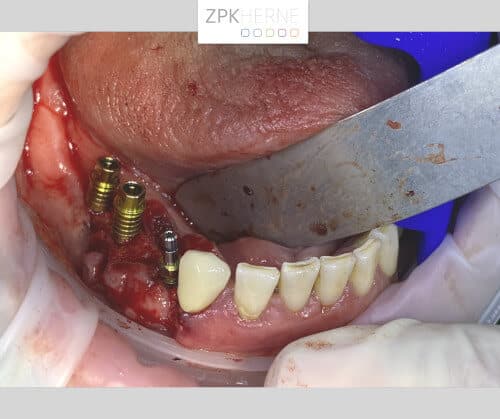

Zur Vorbereitung auf den Tag der Operation wird eine Bohrschablone auf Basis der DVT-Planung angefertigt. So werden die genauen Positionen der einzelnen OP-Schritte festgehalten, damit keine Nervverletzung entsteht. Der chirurgische Eingriff findet unter Vollnarkose statt, hier ist genaueste Konzentration gefragt. Zunächst wird das OP-Gebiet gründlich gereinigt, damit keine Bakterien in die Wunde gelangen. Nun Schnittführung auf den Kieferkämmen: Das Gewebe wird vorsichtig abgelöst und der Knochen freigelegt. Die Bohrschablone wird anprobiert und die Bohrungen für die Implantate Schritt für Schritt durchgeführt. Die Implantate werden nach und nach maschinell eingebracht und radiologisch kontrolliert. Währenddessen wird eine mit Blutplättchen und Wachstumsfaktoren angereicherte Fibrinmembran (LPRF) hergestellt, indem eine gewisse Menge Blut des Patienten zentrifugiert wird. Dies dient der besseren Wundheilung und ist unter dem Begriff „Eigenbluttherapie“ als besonders schonende und effiziente Behandlungsmethode bekannt.